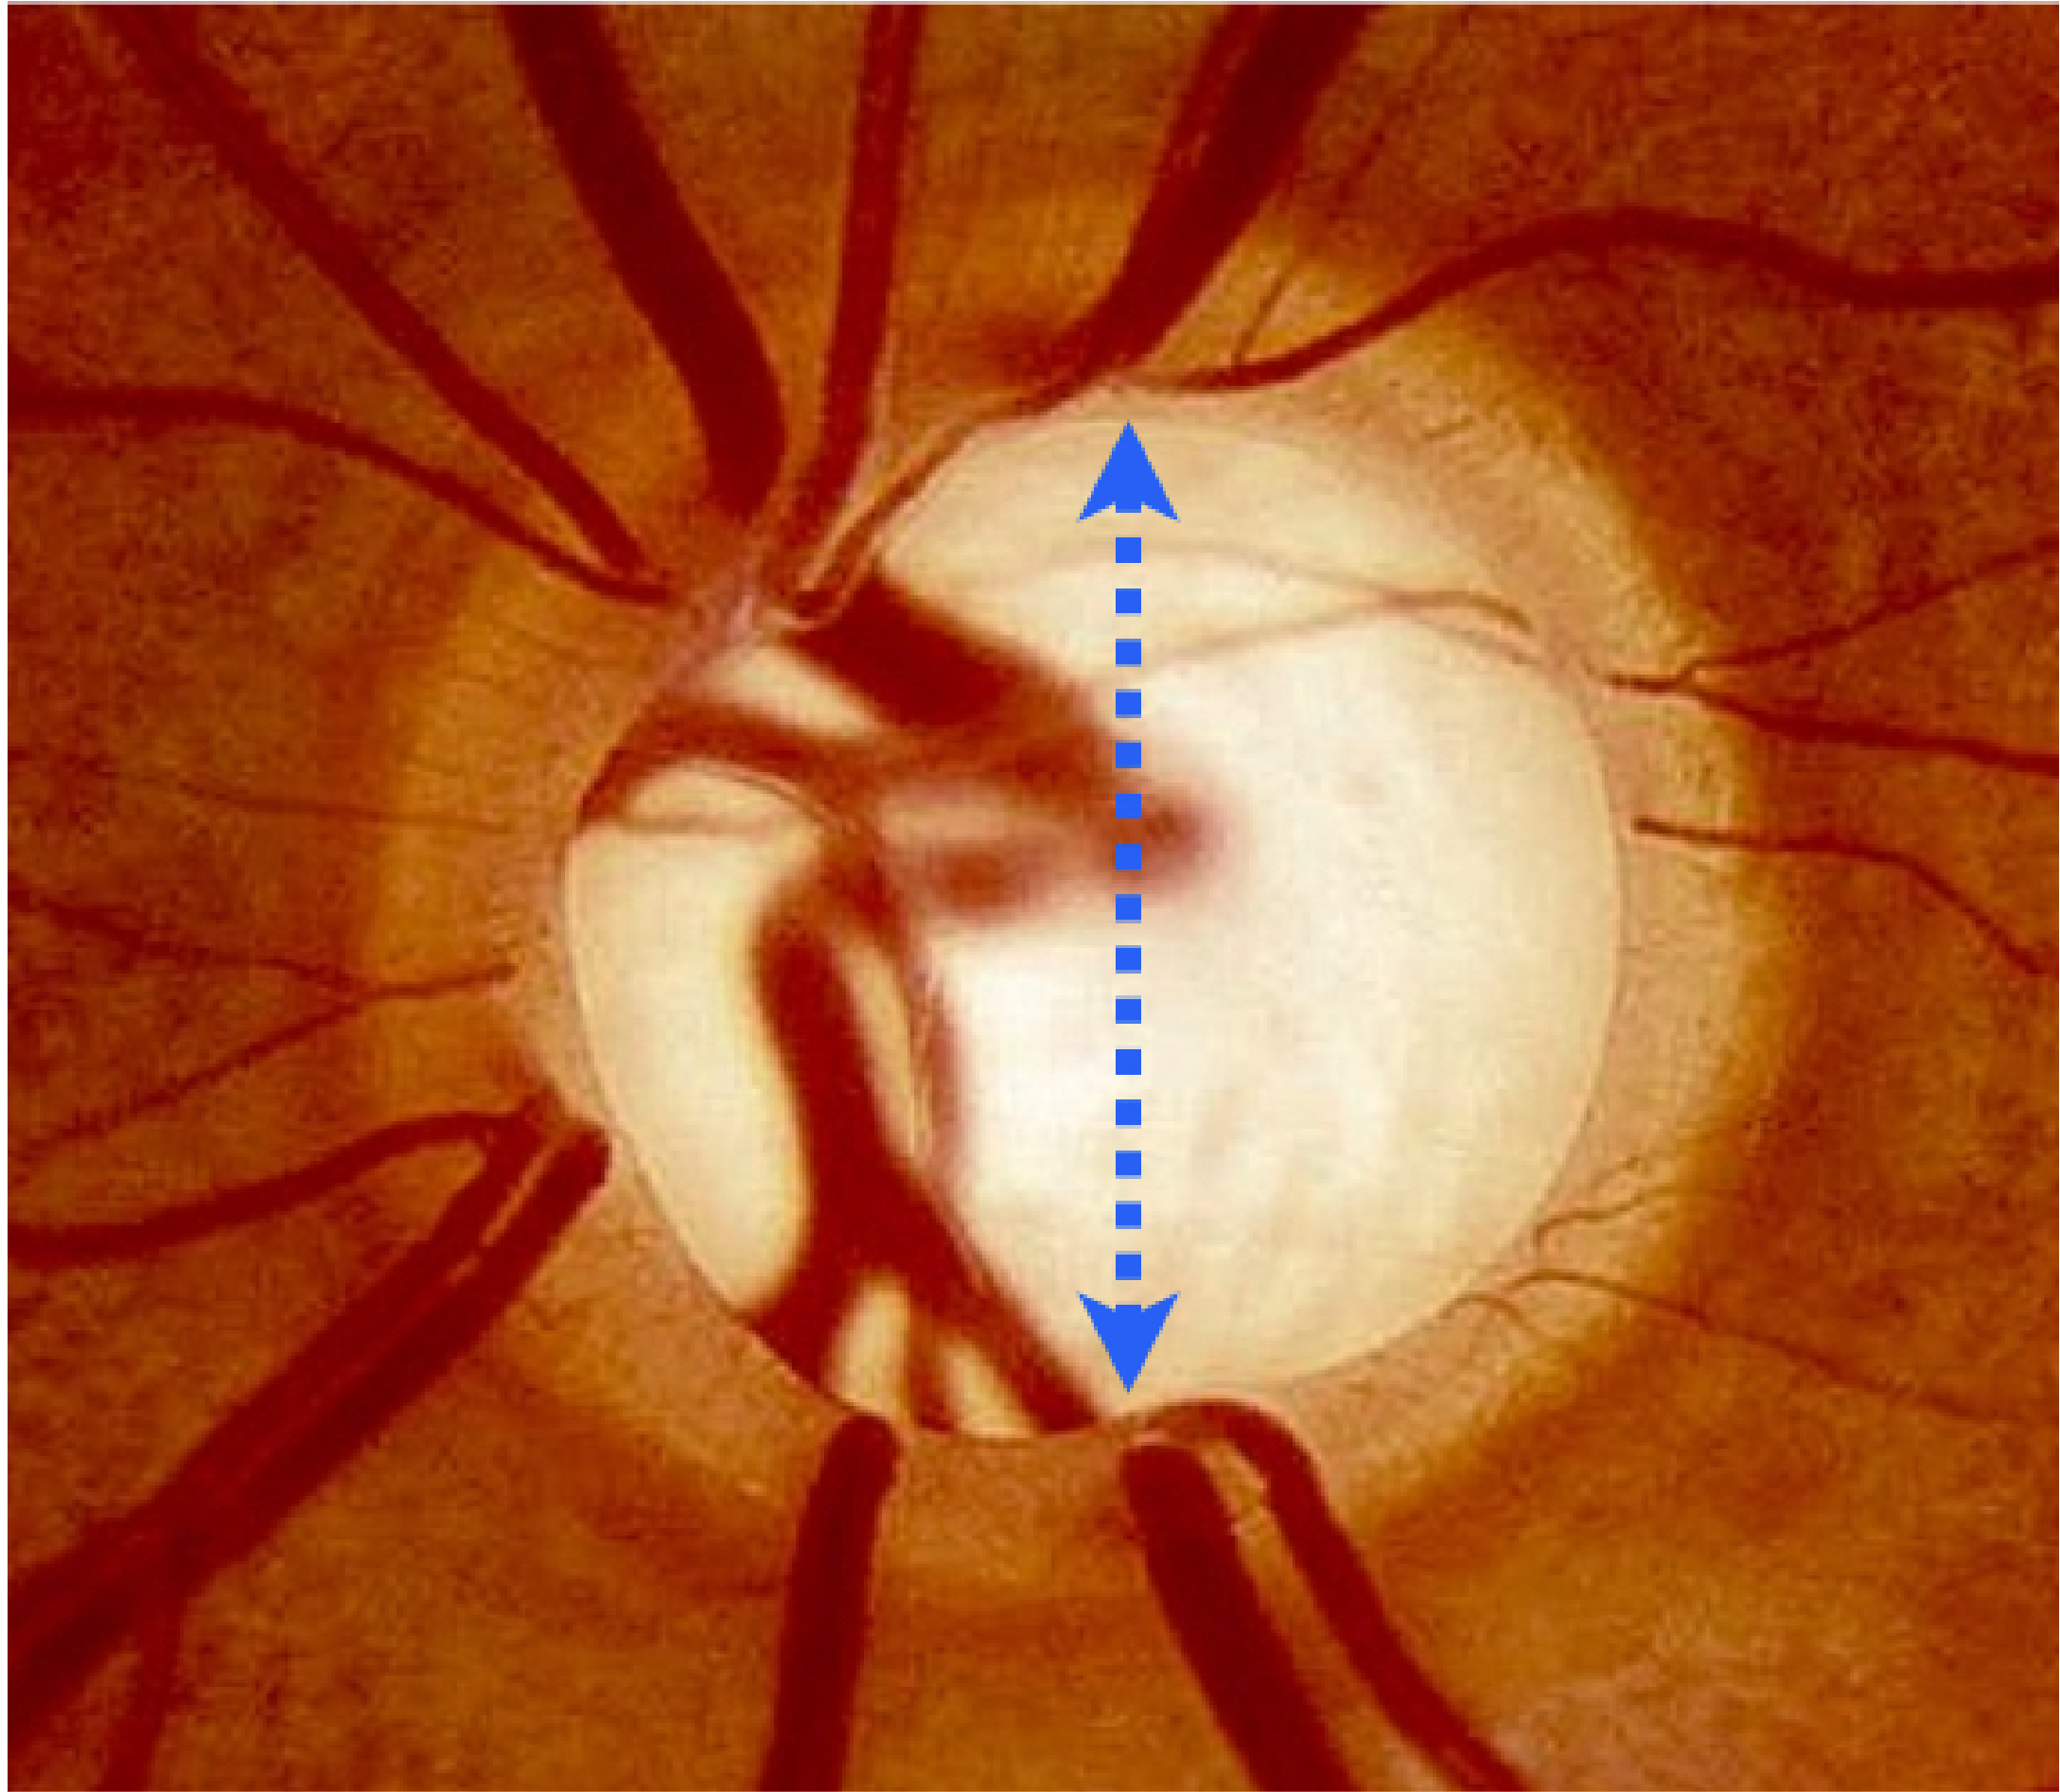

Glaucoma refers to the progressive destruction of vision nerve fibres that transmit signals to the vision processing centre of the brain. These nerve fibres are very sensitive to the pressure and blood supply within the eye. If both the eye pressure and blood supply are poorly regulated, these vital nerve fibres gradually die off, leading to permanent loss of vision.

Testing includes Visual filed assessment, Optic nerve fibre digital scans and photographic analysis, as well as eye pressure & structural assessment. If you have glaucoma, treatment can begin immediately to preserve your vision. It is a chronic condition that must be monitored for life.

It is important to remember that although there is no cure for glaucoma, there are several effective glaucoma treatments for preventing any further loss of vision. The appropriate treatment depends on individual factors that Dr. Djan will discuss with you during your consultation with specialised diagnostic tests. These factors include how high the eye pressure is, the magnitude of vision loss, the critical health of the nerve fibres (optic nerve) and the type of glaucoma you have. The armamentarium of treatment options for glaucoma includes: